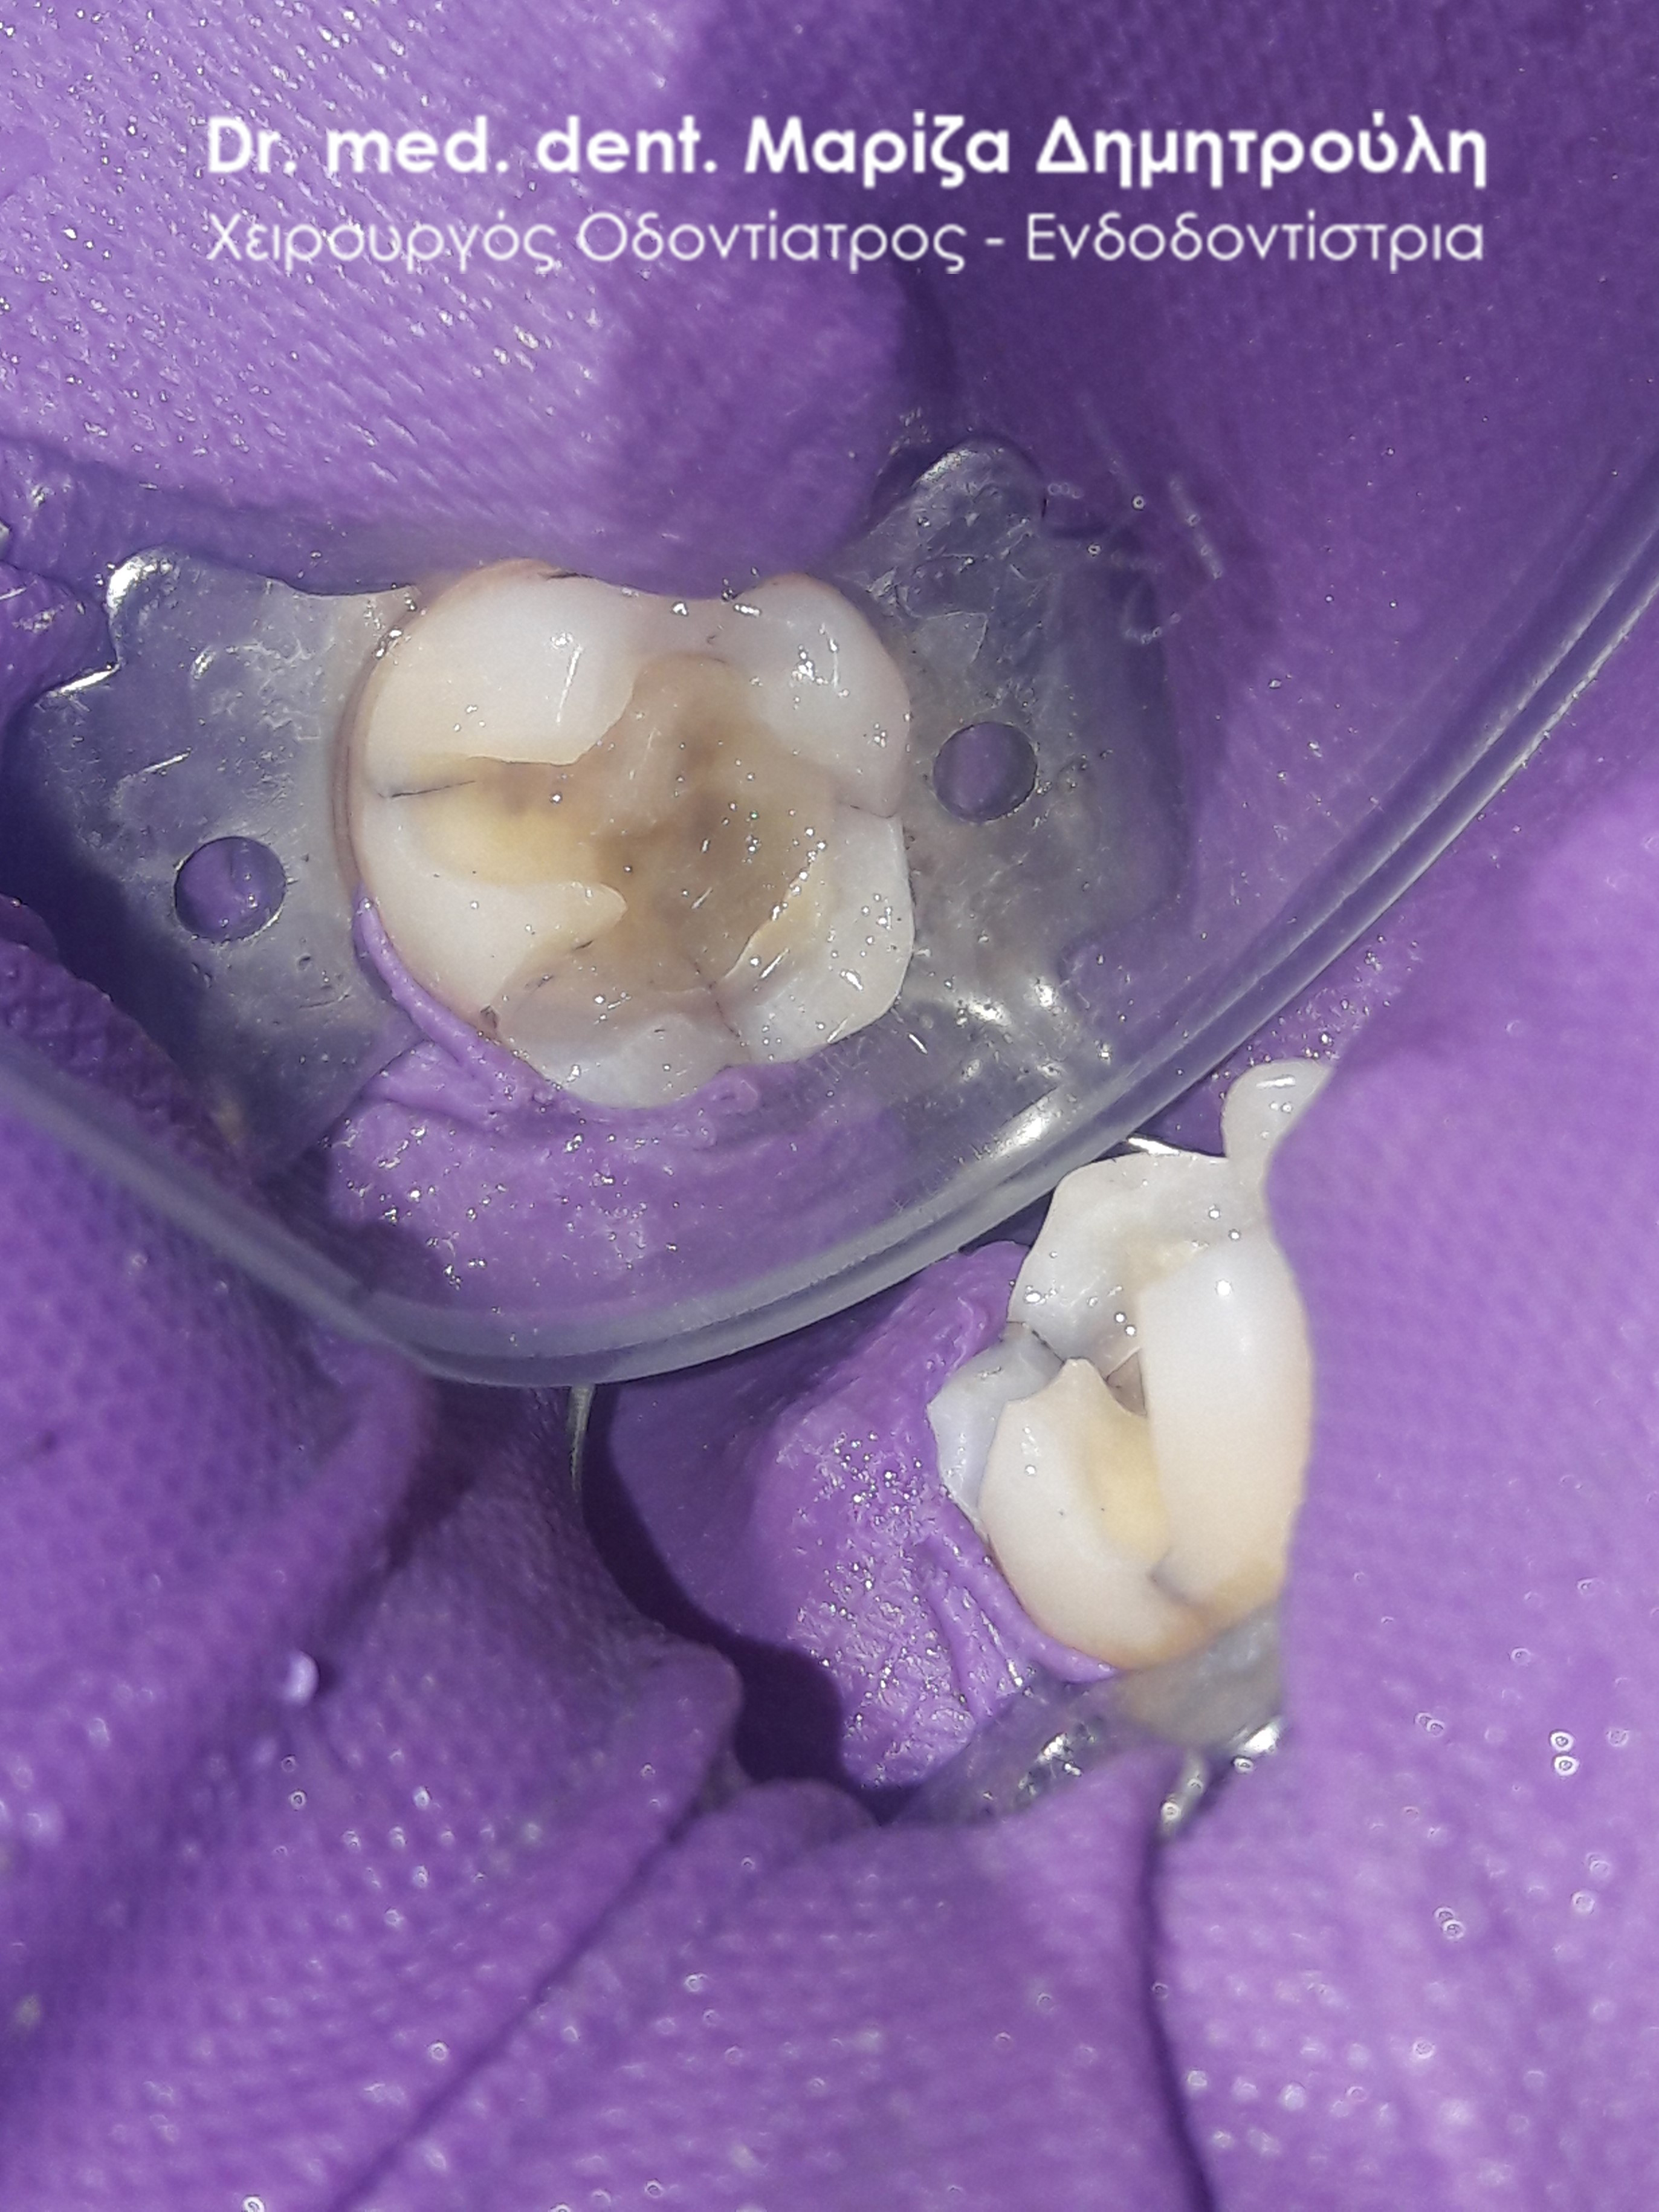

Στο παρόν περιστατικό απουσιάζει η αρχική εικόνα των δύο δοντιών πριν αρχίσει ο εκτροχισμός τους. Διαθέσιμες είναι μόνο η ενδιάμεση εικόνα που παρουσιάζει το εύρος του οδοντικού ελλείμματος στα δύο γομφίους της αριστερής πλευράς της άνω γνάθου και η τελική εικόνα αποκατάστασης των δύο δοντιών.

Η ασθενής αισθανόταν τις τελευταίες μέρες έναν ήπιο πόνο κατά τη μάσηση τροφών. Μετά την κλινική εξέταση του στόματος διαπιστώθηκε η ύπαρξη τερηδονικών κοιλοτήτων στους δύο άνω αριστερούς γομφίους. Αποφασίστηκε με τη συναίνεση της ασθενούς η αντικατάσταση των σφραγισμάτων. Στον πρώτο γομφίο διορθώθηκε μόνο η μισή έκταση του παλιού σφραγίσματος, καθώς κρίθηκε οτι δεν ήταν απαραίτητη η αφαίρεση ολόκληρου του παλιού σφραγίσματος.

ΠΡΙΝ

META